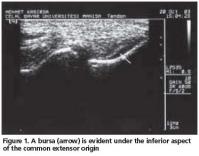

Tendon echotexture was accepted to be normal if a uniform fibrillar pattern could be traced between the muscle and the attachment to the lateral condyle. Tendinopathy was described if there was a loss of this normal fibrillar pattern that is seen as focal areas of hypoechogenicity. A partial tear was defined as a focal anechoic area with no fibers intact or an echogenic irregular band that could run either horizontally or longitudinally in the common extensor origin. A complete tear was defined as a distinct complete interval traversing or extending through the full width of the common extensor origin. Confirmation of the abnormality was performed by imaging at least the two planes. Enthesopathy was diagnosed if the proximal part of the common extensor origin was enlarged and there were echogenicity alterations. Focal areas of calcification and thickening of the peritendinous lining (peritendinitis) were recorded, and bursitis on the inferior surface of the extensor carpi radialis brevis tendon was noted[1,4,16].

Fifty-two patients (39 women, 13 men; mean age: 47.5 years [SD 9.6]) with LE participated in this study. US examinations in 24 (46.2%) patients were normal (Group 1). Initial clinical diagnosis of LE was confirmed by US in 28 (53.8%) patients (Group 2). US pathologic findings were: tendinopathy (n: 25, 89.2%), partial tear (n: 5, 17.9%), enthesopathy (n: 4, 14.3%), focal areas of calcification (n: 5, 17.9%), peritendinitis (n: 3, 10.7%), and bursitis (n: 3, 10.7%) in Group 2 patients (Figures 1,2, 3). Three patients had partial tear or enthesopathy or peritendinitis alone without tendinopathy. All of the bursitis was accompanied with a partial tear. We did not detect a complete tear of the common extensor origin.